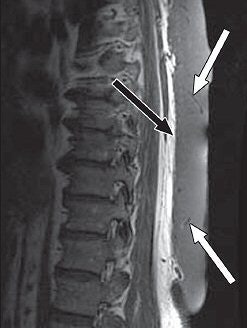

| A 65-year-old man with plaque-like diffuse neurofibroma. Above, sagittal T1-weighted MR image (TR/TE, 500/16) shows thick plaque-like diffuse neurofibroma involving skin and subcutaneous tissues of back. Deep aspect (black arrow) of mass is well-defined, and deeper subcutaneous tissues are uninvolved. Small flow voids (white arrows) reflect prominent internal vascularity. Below, sagittal T2-weighted MR image (3,200/104) shows diffuse neurofibroma (white arrows) that is markedly hyperintense in relation to muscle (black arrow). |

On the T1-weighted MR studies, signal intensity was similar to or mildly higher than that of skeletal muscle. On T2-weighted imaging, lesions were either mildly or markedly hyperintense to muscle. Enhancement was universally intense on contrast-enhanced MR.

Attenuation on unenhanced CT varied, from lower than that of skeletal muscle, similar to skeletal muscle, and similar to fat. On contrast CT, attenuation was similar to muscle. Absolute enhancement could not be determined because no patient had both types of CT studies. Finally, on ultrasound, the neurofibroma exhibited hyperechoic plaque-like involvement.

"MR imaging was best at defining the extent of the lesion and, with its superior contrast resolution, best able to distinguish the diffuse neurofibroma from adjacent, noninvolved structures," Hassell explained. "Standard MR tumor protocols, including T1-weighted, T2-weighted, and postcontrast T1-weighted images, should be adequate for evaluation of diffuse neurofibromas.... CT and ultrasound can also be used to evaluate diffuse neurofibroma lesions and can guide biopsy."